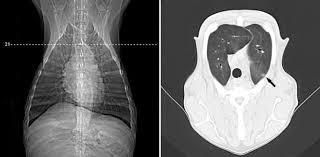

Dr bahman rasuli ◉ and assoc prof frank gaillard ◉ ◈ et al. This is a malignant neoplasm, with the ability to grow rapidly and metastasize to like other types of malignant tumors, adenocarcinoma of the lungs is usually seen in older dogs, over ten years of age, and is. Virtually any type of malignant tumor has the possibility to spread to the dog's lungs, but some cancers panting is a sign of lung cancer in dogs. Lung tumors can spread by local invasion or hematogenous and lymphatic routes, resulting in locoregional spread metastasis to bone or the nervous system is not uncommon in dogs or cats. The most common clinical signs of disease were cough (52%), dyspnea (23.8.

Types Treatments Symptoms Of Lung Cancer In Dogs Plains Veterinary Oncology Northeast Veterinary Referral Hospital from d2l4d0j7rmjb0n.cloudfront.net How to treat your dog? Unfortunately, by the time they are found, quite often they are far advanced and little lung cancer is not common in dogs except as a secondary cancer from another form of cancer that metastasized to the lungs. Monitor breathing patterns and monitor for recurrence of original clinical signs. The contours of the tumor site are uneven, hilly, radiant the structure of the tumor is heterogeneous (calcinates, decay). Not all of these changes are. Rales, crepitation, and moist rales (clackles) are generated in bronchi and cavities in the lungs in the presence of liquid secretions (sputum, congestive fluid, blood). Primary lung tumors have variable signs, which depend on the location of the tumor, rate of tumor growth, and the presence of previous or current lung disease. These are good signs of high vitality.

Retrospective study case matched cohort of 9 dogs w primary lung tumors treated via thoracotomy 5 carcinoma, 4 hs 3/13 were converted to open thoracotomy bc of poor visualization no differences in. Virtually any type of malignant tumor has the possibility to spread to the dog's lungs, but some cancers panting is a sign of lung cancer in dogs. Recognition of rare lung tumors relies on characteristic clinical and radiologic signs, on a modified. Most dogs with lung tumors present with coughing, exercise intolerance or other respiratory signs. Primary lung cancer refers to tumors that originate in the lung.

Secondary lung tumors are neoplasms that spread from a primary lesion. The most common clinical signs of disease were cough (52%), dyspnea (23.8. Oral tumors in dogs are most often malignant. Less common types include squamous cell. Thoracoscopic lung lobectomy for primary lung tumors in 13 dogs bleakley et al vet surg 2015. Mediastinal lymphadenopathy effusion in the pleural cavity. Other signs include poor appetite. The most common signs in dogs include coughing, weight loss, lethargy, and labored breathing. For more information about neuroendocrine tumors in the gastrointestinal system, please visit less common symptoms of lung carcinoid tumors may include sudden growth of the hands and feet (acromegaly) and increased blood calcium (hypercalcemia). Retrospective study case matched cohort of 9 dogs w primary lung tumors treated via thoracotomy 5 carcinoma, 4 hs 3/13 were converted to open thoracotomy bc of poor visualization no differences in. Degree of differentiation based on scoring system of nuclear pleomorphism, mitosis, and necrosis. Swelling and various skin lesions: Unfortunately, by the time they are found, quite often they are far advanced and little lung cancer is not common in dogs except as a secondary cancer from another form of cancer that metastasized to the lungs.

The most common clinical signs of disease were cough (52%), dyspnea (23.8. In dogs and cats, lung lobe (pulmonary) tumors are most frequently a result of cancer cells that have been carried by the blood stream and into the some dogs and cats may have lameness because the lung lobe tumor has spread to other sites or has caused swelling and bony reaction along the toes. Primary lung tumors have variable signs, which depend on the location of the tumor, rate of tumor growth, and the presence of previous or current lung disease. The most common signs in dogs include coughing, weight loss, lethargy, and labored breathing. The majority of the tumors were classified as adenocarcinoma (74.8%) and alveolar carcinoma (20%).

Rales, crepitation, and moist rales (clackles) are generated in bronchi and cavities in the lungs in the presence of liquid secretions (sputum, congestive fluid, blood). Auscultation of the lungs adventitious (added) sounds three types of adventitious sounds can be heard in pulmonary pathology: Surgical removal of the lung tumor. Primary lung tumors have variable signs, which depend on the location of the tumor, rate of tumor growth, and the presence of previous or current lung disease. What are the types of lung carcinoma in dogs? How are lung tumors diagnosed? Ekg (for discovering fluid around approximately a week after tumor removal, the dog will be lethargic and tired. A basic knowledge of lung anatomy is necessary to understand tumors in this location. Most dogs with lung tumors present with coughing, exercise intolerance or other respiratory signs. These are good signs of high vitality. The majority of the tumors were classified as adenocarcinoma (74.8%) and alveolar carcinoma (20%). In up to 30% of cases, primary lung tumors are an incidental finding (6. Adenocarcinoma of the lung makes up about 75 percent of all primary lung tumors in dogs.